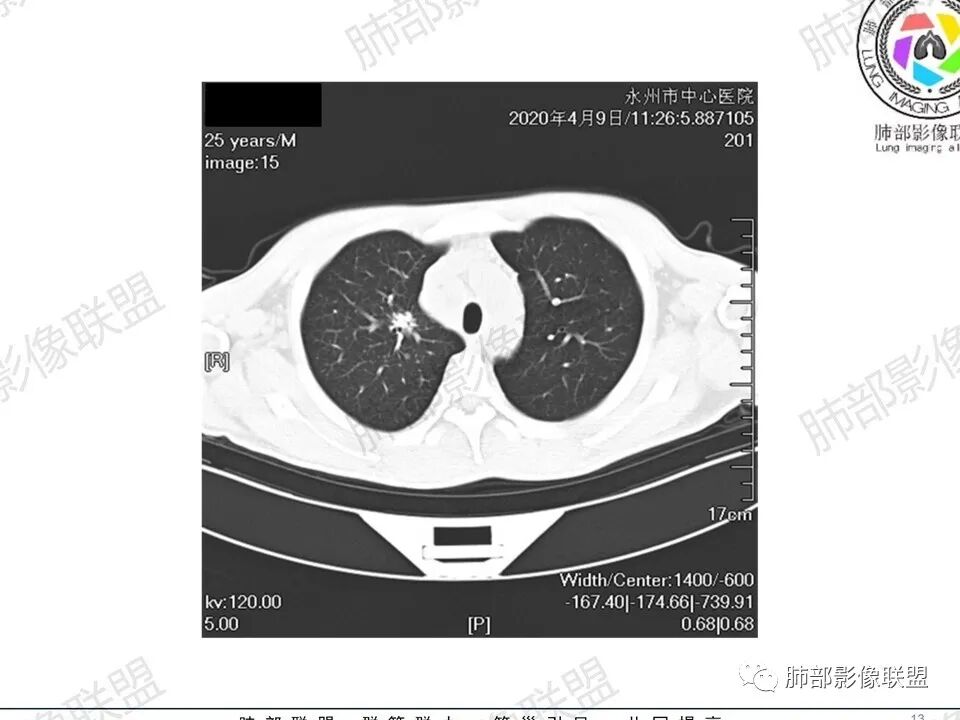

那个人:青年男性,慢性病程,咳嗽气促,伴盗汗胸痛。实验室,贫血,血沉快,C反应蛋白升高,低蛋白血症。影像,双肺散在斑片影,结节影,伴树芽,斑片影源支气管血管束分布,支气管走形自然,结节影有小空洞,有些周围有磨玻璃成分,小结节有些成串珠样改变,纵隔肺门淋巴结肿大,心腔低密度。考虑淋巴增值类疾病,结核?淋巴瘤?结节病?鉴别血管炎,实验室,影像不太支持

一切∮随缘:双肺多发大小不等结节,结节密度高,边缘清楚,部分结节内可见血管穿行,另右肺长条状实变影,内部可见支气管充气征,局部支气管壁增厚,双肺多发小树丫,双肺门及纵隔淋巴结肿大,部分融合,无增强,对淋巴结坏死无法判断,临床:年轻男性慢性病史急性加重,血象、CRP、ESR高,考虑一元论:结核(年龄加影像都符合),二元论:结节病或淋巴瘤+结核(建议CT增强及淋巴结穿刺),无原发肿瘤病史,癌性淋巴管炎代排。

Coke with ice :25岁。支气管血管束分布为主,同时有淋巴管型分布的小叶中心型结节。周围间质微小结节。中央带明显,右侧明显,中上肺明显。中央带向周围放射状分布。有空气潴留,支气管充气征,病变周围少于磨玻璃。双肺门纵膈多大淋巴结肿大。常规疾病谱:结节病,结核,荚膜组织包浆菌,淋巴瘤,还有卡波西肉瘤。诊断:结节病第一位,淋巴瘤第二位。查艾滋病,卡波西肉瘤第三位。

3、影像表现:双肺散在斑片影及结节影,部分结节内可见血管穿行,斑片影沿支气管血管束分布,近胸膜侧病变收缩不明显。部分中央淋巴间质增厚,小叶间隔增厚。病灶内支气管穿行,部分支气管略扩张。局部小结节呈串珠样改变。纵隔、肺门区、锁骨上及腋窝淋淋巴结肿大,部分有融合。心腔低密度。脾大。

2.双肺多发片影及结节影,边界可分辨,右肺中上叶较为密集,没有胸膜下分布优势。病灶实性密度为主,未见钙化及液化。

3.右肺较多微小结节,密度较为浅淡,部分沿血管束分布,未见沿小叶间隔及叶间裂分布结节影,未见典型的终末气道树芽。

4.病灶区域穿行支气管显示良好,未见壁增厚及管腔狭窄。

5.双肺门及纵隔淋巴结显著增大,这改变相当显眼。这里强调“双肺门”及“多发”!

淋巴瘤肺部浸润表现多样,多发结节影是其最常出现的影像学改变,尤其是霍奇金病。

2.右肺多发微小结节影,部分沿血管束分布,尽管未见小叶间隔改变,但双肺门淋巴结增大确实应当首先排除结节病,但经验上说,结节病的增大淋巴结密度往往较高、较密实,边界往往清楚,“独立性”很强,绝无“融合之嫌”!此外,较少出现贫血、脾大,临床表现也往往较轻微。

3.双肺多发结节影,没有明显的新旧不等,没有钙化,微小结节影密度偏低,边缘不够僵硬锐利;病灶区域穿行支气管显示良好,未见壁增厚及管腔狭窄,加之病灶如此广泛,病灶未见收缩、肺叶体积未见缩小,结核中毒症状不明显等等都不支持结核。